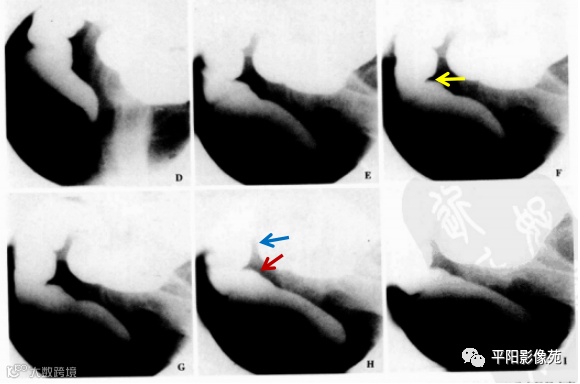

盆底痉挛综合征(spastic pelvic floor syndrome,SPFS):指用力排粪时盆底肌肉痉挛收缩而不松弛的功能性疾病。排便造影表现为力排时肛直角不增大,仍保持在90°左右或更小,且多出现耻骨直肠肌痉挛压迹(PRMI),即可诊断本病。合并直肠膨出时100%出现“鹅征”:即将力排片竖摆显示:直肠膨出为“鹅头”,肛管为“鹅嘴”,变细的直肠远段为“鹅颈”,直肠近段和乙状结肠为“鹅身”,宛如一只鹅,称为“鹅征”。(图 6,图7)

图6 力排相肛直角小于90°,钡剂排不出,直肠前缘突出,局部形态近似“鹅头”

图7 D~I.力排相,每秒1帧,ARA渐变小,并出现耻骨直肠肌痉挛压迹(黄箭)和直肠膨出(红箭)状如“鹅头”,力排时直肠远段变细(蓝箭)宛如鹅颈。